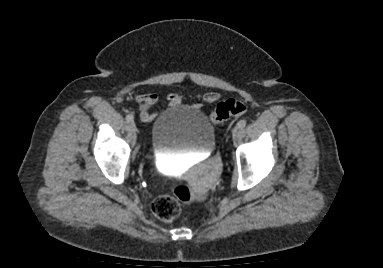

Мультиспиральная компьютерная томография органов малого таза включает в себя исследование женских половых органов (матка, яичники) или мужских половых органов (предстательная железа, семенные пузырьки, семявыносящие протоки), а также мочевого пузыря с мочеточниками на видимом протяжении, прямой кишки, тазовой брюшины, лимфатических узлов, мягких тканей малого таза.

Нативная компьютерная томография таза проводится без использования контраста. Однако при подозрении на патологические изменения со стороны органов мужской или женской половой сферы, мочевыделительной системы, прямой кишки или окружающих мягких тканей, обязательным является внутривенное введение йодсодержащего контрастного препарата. Контрастный препарат в большей степени накапливается в патологически измененных участках и обеспечивает их яркую визуализацию на фоне здоровых тканей. Это используется для диагностики онкологических заболеваний на ранних стадиях, что имеет решающее значение для жизни и здоровья пациента.

В результате получаются снимки тончайших срезов исследуемой зоны с высокой степенью детализации, на основе которых производится объемная реконструкция органов малого таза, что позволяет проводить точную диагностику. Трехмерные модели дают информацию о пространственном расположении органов и патологических образований, что важно, например, при планировании оперативных вмешательств и в дальнейшем при оценке эффективности операции и проведенного лечения.

Мультиспиральная компьютерная томография используется для диагностики аномалий развития, травматических повреждений, воспалительных заболеваний и опухолевых процессов органов малого таза. Преимуществами данного исследования является высокая скорость сканирования и доступная цена. Однако в ряде случаев может быть более предпочтительно выполнение магнитно-резонансной томографии, которая обладает высокой чувствительностью и информативностью для обследования органов и мягких тканей малого таза. В клинике «Доступная медицина» МРТ малого таза можно пройти на нашем современном оборудовании экспертного уровня.